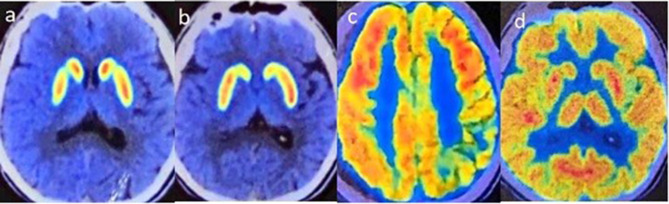

Results: Specifically, muscle rigidity in ALS is characterized by a velocity-dependent increase in muscle tone caused by damage to the upper motor neurons. This symptom tends to be more pronounced in the lower limbs than in the upper limbs and is often accompanied by spastic gait. Objective examinations may reveal early atrophy of the frontal and temporal lobes of the cerebrum on head magnetic resonance (MR) imaging, whereas 18F-FDG brain positron emission tomography (PET) may reveal reduced metabolism in the frontal and parietal lobes of the cerebrum with normal basal ganglial function, distinguishing ALS from basal ganglial metabolic decline in MSA.

Discussion: To our knowledge, this is the first case of ALS misdiagnosed as MSA. Clinically, patients with parkinsonism who do not respond to dopaminergic drugs should be cautious about atypical ALS. Muscle rigidity manifesting as upper motor neuron damage, and MR and 18F-FDG brain PET imaging can provide early differential diagnosis indicators.